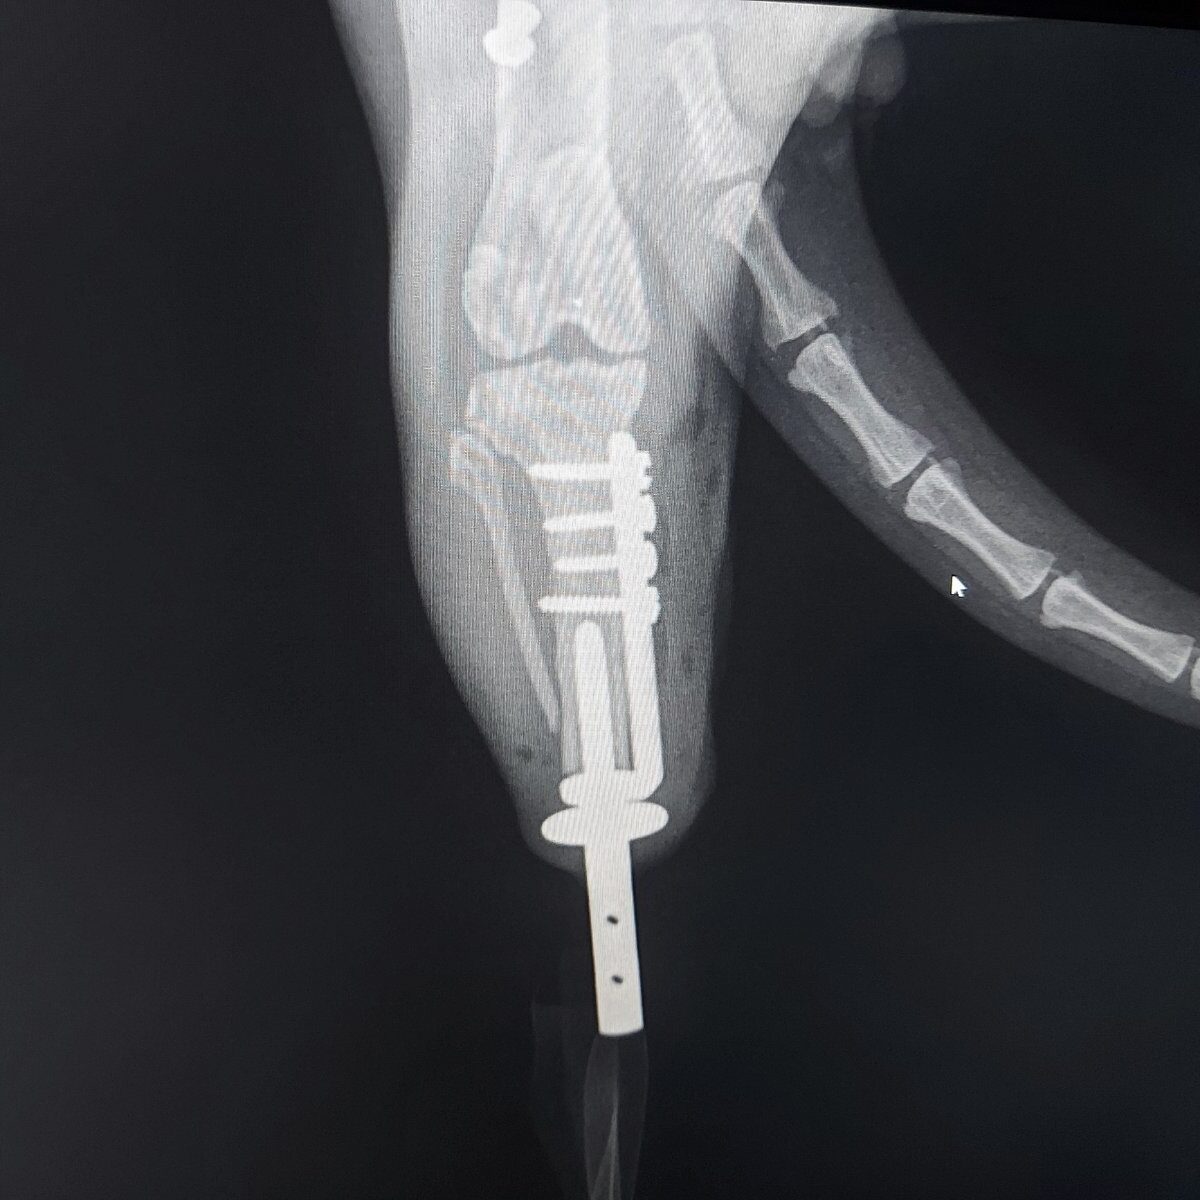

Custom-made implants

Customizing veterinary is the future. Our engineering team is ready to create every implant geometry and shape that will fulfil your highest requirements. All implants are developed with advanced CAD-CAE Systems and produced with 3D-Printing technology using Titanium (Ti6Al4V) and PEEK (PolyEtherEtherKetone) materials.

We have designed several types of customized implants such as ITAP, vertebrae, arthrodesis plates and PGR. At bio3Dtech we believe that the key to success in complex orthopedic cases is customization.